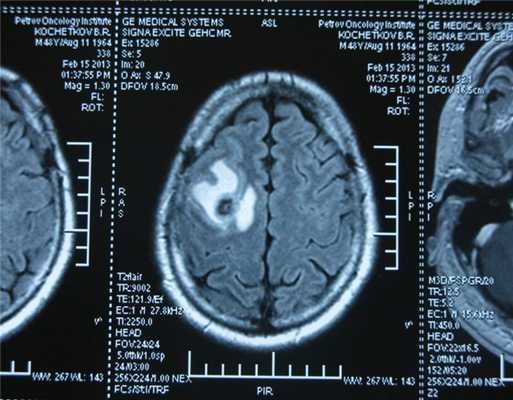

Также выполняют МРТ головного мозга, чтобы выявить наличие метастазов в нем.

![Метастаз в головной мозг при герминогенных опухолях (МРТ головного мозга)]()

Метастаз в головной мозг при герминогенных опухолях (МРТ головного мозга)

![Метастаз в головной мозг при герминогенной опухоли]()

Рисунок 9. – метастаз в головной мозг при герминогенной опухоли.